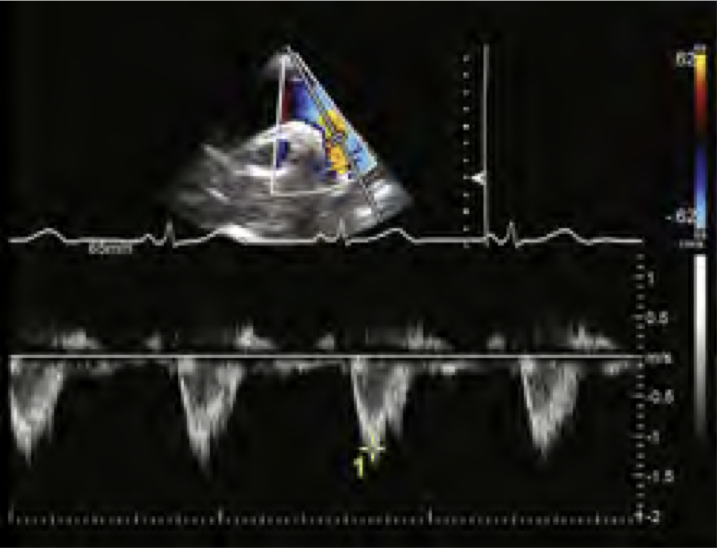

Q

What normal flow pattern is this and in what view?

A

descending AO Thoracic, SSN/Subcostal